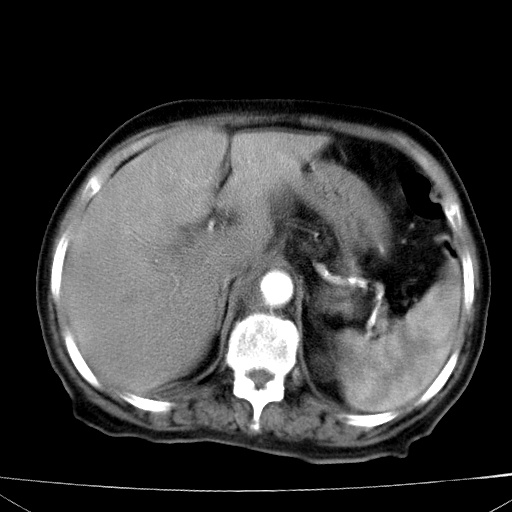

网站人气太旺!昨天的帖子就沉到海底,只好再发贴!ct18338:女 78岁,肝胆病变,已增强,再会诊!原帖链接:http://www.radida.com/bbs/forum.php?mod=viewthread&tid=50032

1)考虑胆囊癌侵犯肝脏并肝门区、腹膜后及右侧膈角后淋巴结转移。2)肝左叶近肝顶部囊肿。3)肝左叶肝内胆管结石。4)左肾近下极囊肿。